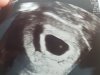

Potrzebuje Waszej porady. Wczoraj ma usg lekarz uwidocznil dużego krwiaka w stosunku do pecherzyka ciążowego. To to czarne ppdluzne pole. Dostałam Luteine 2x1 dopochwowo. I mam się oszczędzać, leżeć w miarę możliwości. Nie ukrywam, że bardzo zmartwila mnie ta informacja. Dotąd żadnych krwawien i boli silniejszych. W maju miałam zabieg lyzeczkowania i usunięcie polipow. Bardzo boję się o tą ciążę. To moja pierwsza. Którąś z Was może miała również tak dużego polipa? Też luteina na podtrzymanie czy może coś więcej? Dziękuję za wszelkie porady.